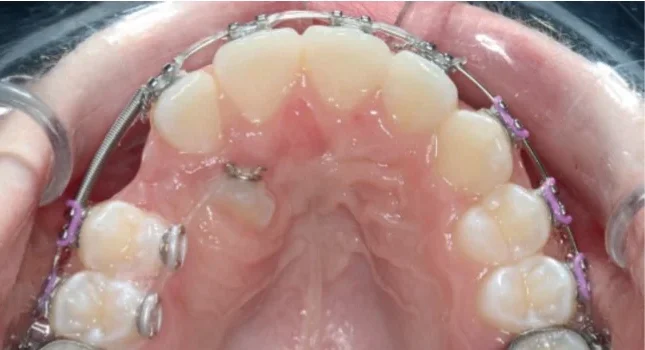

2. Orthodontic Alignment

After exposure, light continuous forces (20–30 g) are applied to move the canine gradually into its proper position. The overall treatment may take 12–24 months, depending on the initial displacement and patient cooperation.